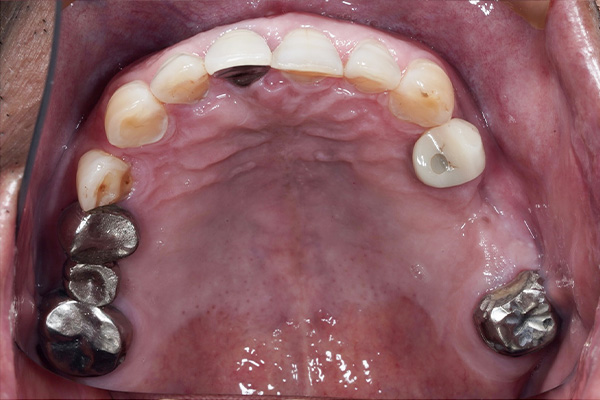

当院のインプラント治療例

― 他院で「難しい」と言われたケースにも対応 ―

※他院で骨量不足と診断された症例です。

【お悩み】

奥歯を失い、他院でインプラントの相談をしたところ「骨が足りないため難しい」と言われ、不安を感じて来院されました。

【診断】

歯科用CTにて詳しく検査を行った結果、インプラントを行うには骨量が不足している状態であることが確認されました。

【治療内容】

骨をつくる治療であるGBR(骨造成)を併用し、将来的な安定性を考慮したうえでインプラント治療を行いました。

【治療後】

現在はしっかり噛める状態となり、日常生活でも違和感なく食事を楽しんでいただいています。

【担当歯科医師からのコメント】

骨が少ないケースでも、CTによる診断と適切な治療計画によりインプラントが可能となる場合があります。

「難しいと言われた」とお悩みの方も、まずはご相談ください。